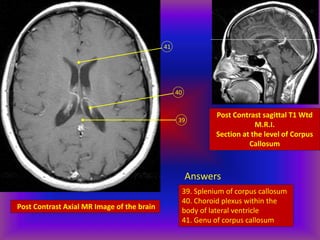

Post Contrast Axial MR Image of the brain

39

40

41

Post Contrast sagittal T1 Wtd

M.R.I.

Section at the level of Corpus

Callosum

Answers

39. Splenium of corpus callosum

40. Choroid plexus within the

body of lateral ventricle

41. Genu of corpus callosum